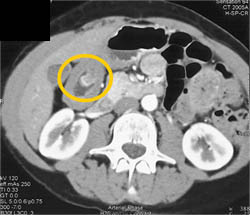

Canada Cronkite Stomach With Multiple Polyps